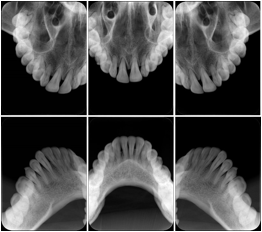

3. A dental provider wishes to capture a series of DICOM IO images for the patient’s dentition. The tooth morphology, teeth are divided into molars, premolars, canines and incisors, and a number of images for each jaw. The anatomic information was captured utilizing the triplet of schema. This standard code sequence is based on ISO 3950-2010, Dentistry - Designation system for teeth and areas of the oral cavity.

Every IO image should have anatomic information either through the primary or modifier sequence.

In most standard cases, images are oriented in structured layouts. These structured displays are useful to be shared between providers for reference purposes.